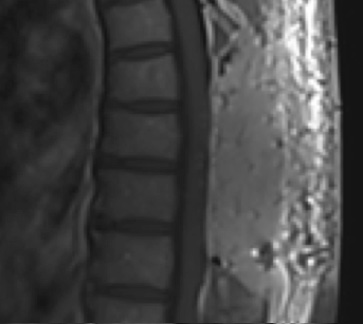

Postoperative MRI T2 illustrating the restoration of CSF surrounding the cord (blue arrow)

Postoperative MRI T1w demonstrating a gross total resection